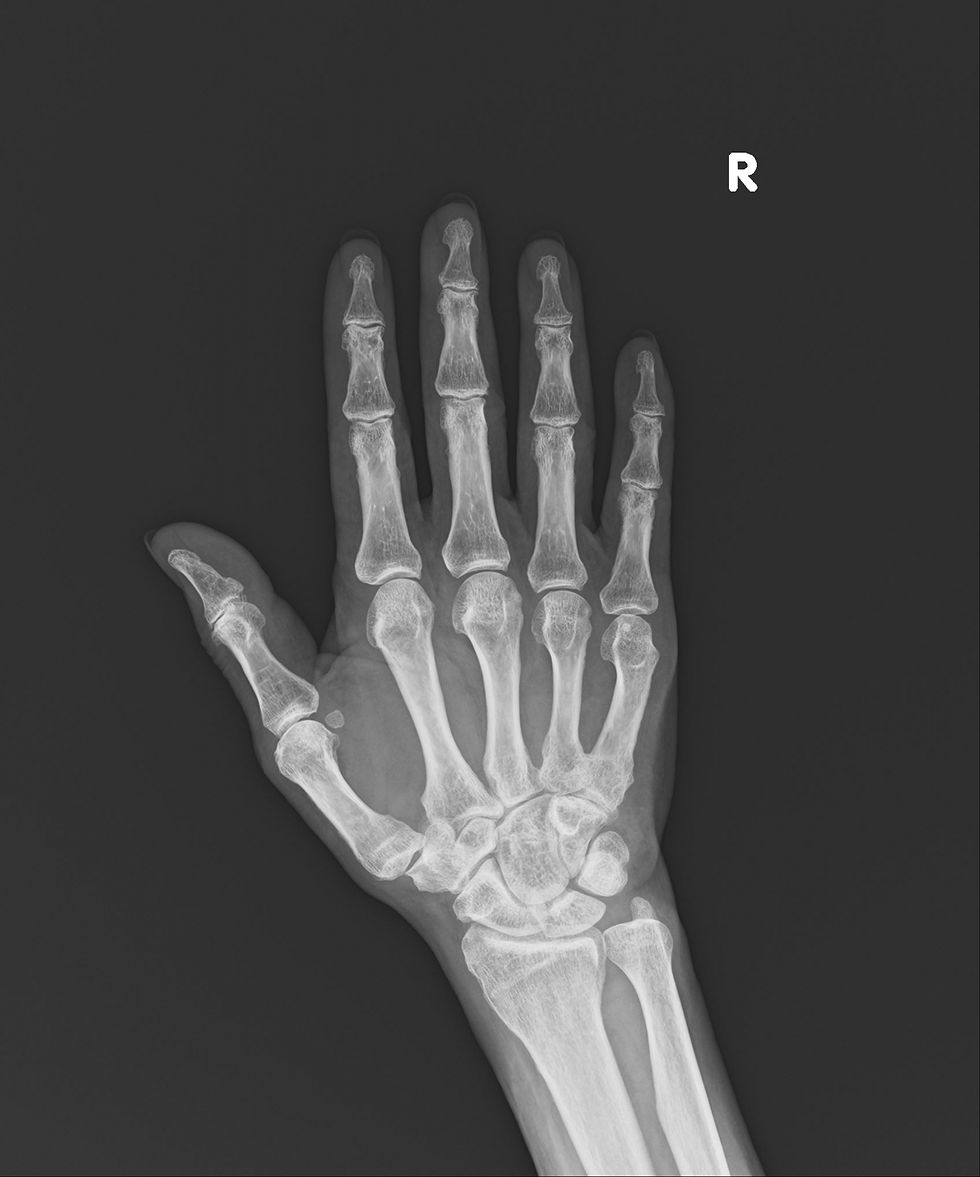

骨折は、手首や脚の付け根、腰に起こりやすく、骨折すると日常生活に大きな障害をきたすだけでなく寝たきりになってしまう事もあります。

また、骨密度の測定にお いては、腕の骨や踵の骨で測定するやり方では信頼性が低いため、当院ではDXA法にてより正確な測定を行っております。

DXA法で腰椎と大腿骨で検査することが一番正確であるといわれており、当院ではDXA法による2か所で検査を行っております。